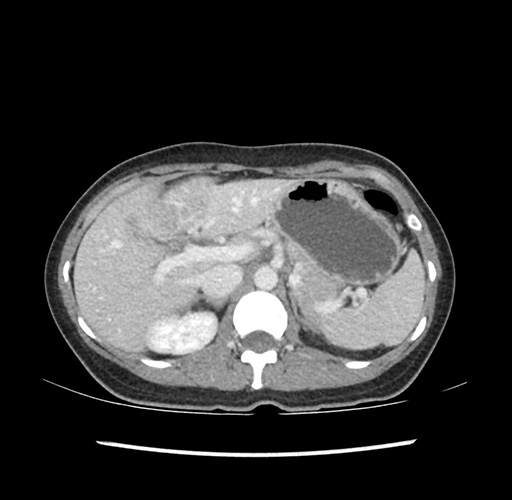

Imaging Analysis

Look through the patient's CT scan to identify any areas of concern for the necessary procedure.

Based on your CT findings, which issue(s) would give reason for "planned slowing down moment(s)" in this case?